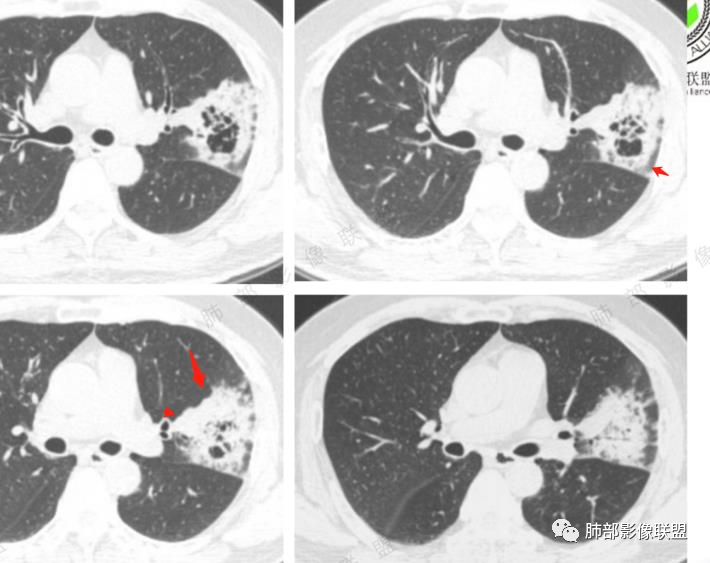

左肺上叶实变影,其内可见多个簇状空洞,大小不一,其内可见分割,多个堆积而成,内外壁光滑,空洞边缘毛糙,可见长索条牵拉胸膜,收缩为主,周围伴有磨玻璃影,随访两个月空洞依旧还在,不知道症状有无减轻,临床培养肺克(是否为致病菌?)有糖尿病,慢性起病,临床炎性指标正常,考虑:1肺癌(假大空,炎性症状不明显都支持)2:真菌(毛霉,无咯血,曲霉)3:GPA(单发少见)4:结核(形态太单一,周围无播散灶)

瘤肺界面清晰,边缘短毛,其内见假大空及空泡,胸膜下多发线条影(胸膜凹陷还是反应性增厚),治疗后两个月没有变化,真菌感染?肺腺癌?

左肺上叶肿块,内可见假大空,多发分隔,肿块膨隆、分叶,边缘毛糙,可见长索条,抗炎治疗无效,首先考虑肿瘤,腺癌可能大

中年男性,糖尿病,左肺上叶团片状高密度影,反晕,边缘毛糙,晕中毛刺,中心分隔,其内可见支气管影,抗炎效果差,2月复查病灶增大,中心密度减低,似空洞形成,首先考虑真菌感染,腺癌待排

56岁男性,有糖尿病基础病。咳嗽咳痰2月,白细胞计数正常。培养出肺炎克雷白菌。胸部CT:左上肺空洞样病灶,厚壁,壁上多量小空泡样密度区,坏死区存留组织(感觉是假大空)。大部分边缘膀隆,部分可见分叶,部分边缘见小叶间隔阻挡;边缘见边界模糊的GGO,主要位于病灶以远处。抗感染治疗后病灶增大。考虑腺癌。

病史两月,炎性标志物不高,肺克基本排除了,空洞内壁光滑,洞壁上可见充气支气管,洞内可见絲状物,抗炎效果不佳,有糖尿病史首先考虑曲霉菌,年龄稍大, 可见胸膜牵拉鉴别一下腺癌

综上,左上肺假大空肿块伴周围实变,边缘似见粘液成分,胸膜牵拉凹陷,但收缩力偏弱,抗感染后两月复查,整个肿块增大,周围实变区增厚。符合腺癌(普通腺癌伴粘液分泌或粘液腺癌可能)